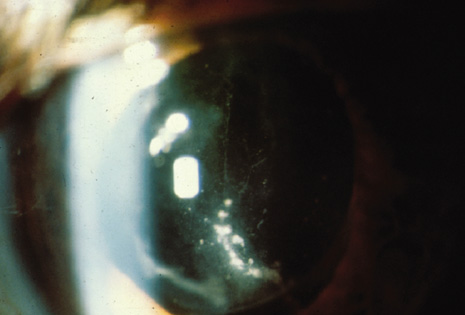

The diagnostic features of infectious endophthalmitis can be divided into two aspects: clinical recognition and microbiologic confirmation. The clinical signs of endophthalmitis vary depending on the preceding events or surgery, the infecting organism, the associated inflammation, and the duration of the disease. In acute-onset postoperative endophthalmitis, when bacteria are the etiologic agents, the hallmark of the clinical diagnosis is marked intraocular inflammation with hypopyon (Fig. 1).1,2 Other signs of acute-onset postoperative bacterial endophthalmitis include fibrin in the anterior chamber and on the intraocular lens, corneal edema, marked conjunctival congestion, lid edema, and vitritis. Retinal periphlebitis is another clinical sign that is diagnostically helpful in eyes with relatively clear media.35 Endophthalmitis caused by fungal organisms generally has less inflammation, a more indolent course, and less ocular pain. Endogenous candida cases often manifest as isolated white infiltrates in the formed vitreous overlying a focal area of chorioretinitis.24,35

Fig. 1. Acute-onset endophthalmitis following clear corneal cataract surgery. The patient shows conjunctival congestion, prominent fibrin in the pupil, and hypopyon.